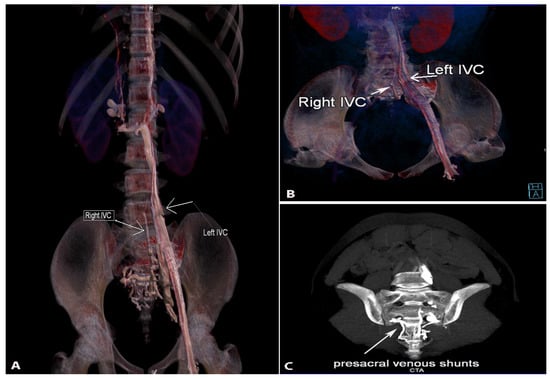

9.4.1. Left Sided Inferior Vena Cava

Surgical Considerations

9.4.2. Duplication of the Inferior Vena Cava